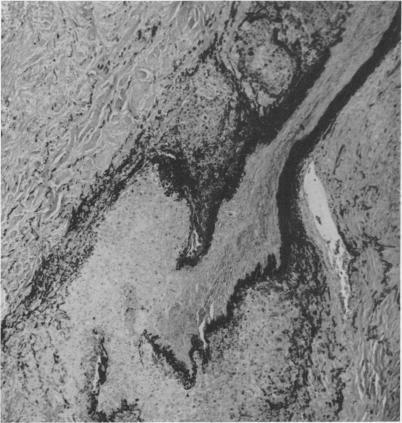

BRONCHOGENIC CARCINOMA: A STUDY OF CASES TREATED AT JOHN HOPKINS HOSPITAL FROM 1933-1958.

Ann Surg. 1965 May;161(5):674-87. doi: 10.1097/00000658-196505000-00005.